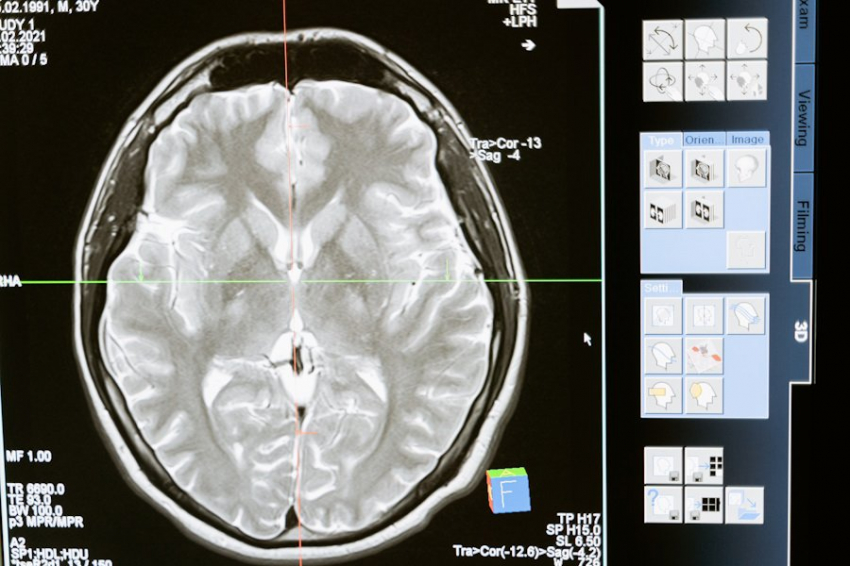

Человеческий мозг может хранить в 10 раз больше информации, чем считалось ранее

Наши воспоминания и мысли возникают из сложных схем электрической и химической активности в мозге. Центральными элементами этой активности являются синапсы, соединения, в которых соединяются ветви нейронов, подобно электрическим проводам. Здесь аксон одного нейрона соединяется с дендритом другого. В этих синапсах нейротрансмиттеры переносят сигналы через щель, инструктируя принимающий нейрон передать электрический сигнал другим. Примечательно, что каждый нейрон может образовывать тысячи таких связей.

В человеческом мозге между нейронами существует более 100 триллионов синапсов. Эти синапсы облегчают передачу информации по мозгу, запуская химические посланники. По мере того, как мы учимся, определенные синапсы укрепляются, позволяя нам сохранять новую информацию. Этот процесс известен как синаптическая пластичность.